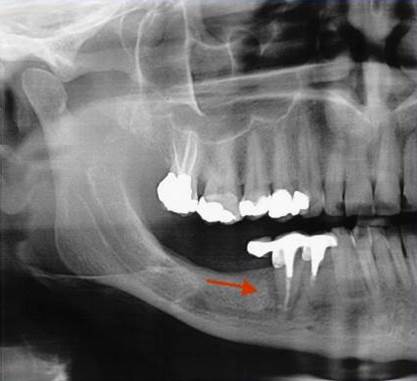

Periometr - první plně automatizovaný přístroj pro zjištění periodontálního statusu pacienta - diagnózy, léčby a profylaxe parodontitidy a dalších onemocnění. Díky správnému určení periodontálnímu statusu pacienta lze včas odhalit a minimalizovat objevující se obtíže.

Používá se i v implantologii, při stanovení diagnózy a léčby periimplantitidy (zánětu měkkých tkání a kosti v okolí implantátu).